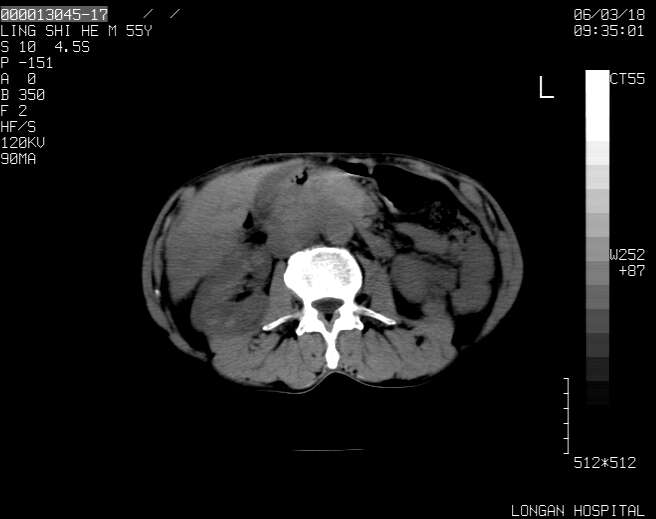

以下是引用guzhongliangddd在2006-3-21 22:13:00的发言:[br]病灶主要位于肝右叶的后份,内见异常血管,门脉主干及右支受侵{提示有癌栓形成},门腔间隙内见增大淋巴结。肝左叶内未见异常。

以下是引用zhuxinli在2006-3-22 1:23:00的发言:[br][br] 病灶主要位于肝右叶的后份,内见异常血管 .门脉右支截断,右叶前段早期强化(考虑动静脉漏),腹膜后肿大淋巴结,病灶逐渐强化,考虑为胆管细胞癌[br]